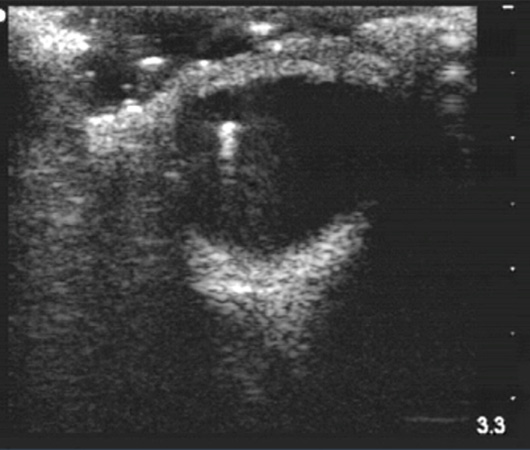

Intraocular Foreign Body

- Intraocular foreign body